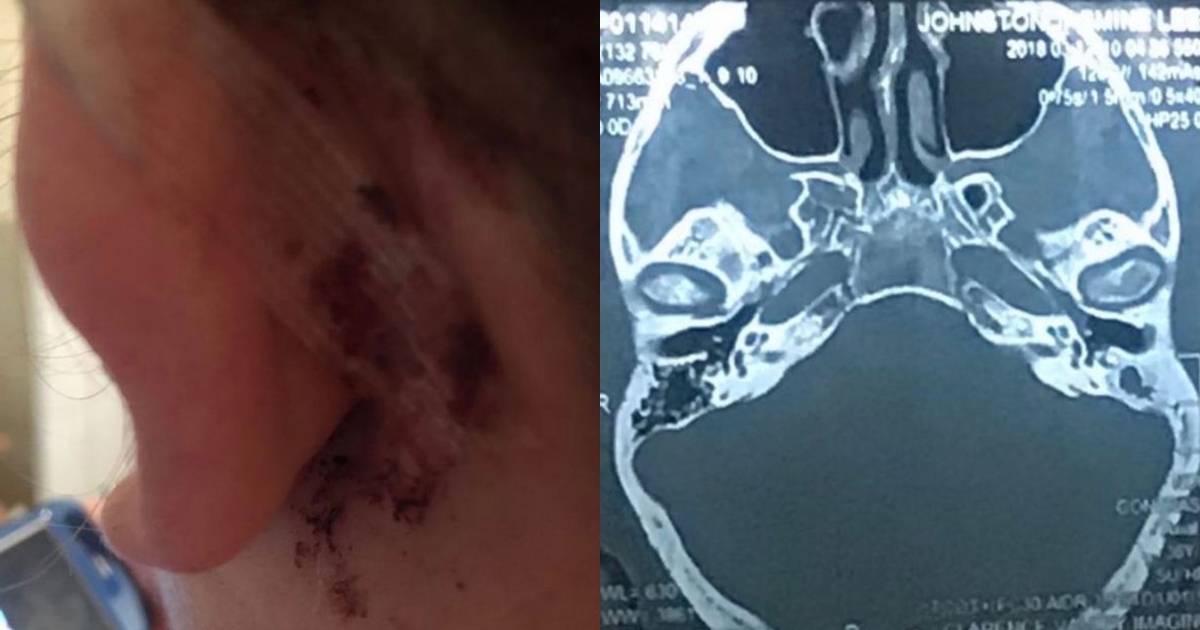

กระทั่งในที่สุด ในปี 2560 จัสมิน ถูกส่งตัวไปพบแพทย์เฉพาะทาง ผู้เชี่ยวชาญด้านหู คอ จมูก โดยภายหลังจากแพทย์ได้ทำการซีทีสแกน ก็มีอันต้องตกใจไม่น้อย เมื่อพบว่า มีการติดเชื้อภายในช่องหูลึก ในจุดที่ใกล้กับสมองมาก อันเป็นผลมาจากเศษชิ้นส่วนสำลีจากคอตตอนบัดที่หลุดเข้าไป

จัสมินเผยว่า แพทย์กล่าวกับเธอว่า ถ้าเธอเอาสำลีแหย่หูไปมากกว่านี้ เธออาจจะตายไปแล้ว แพทย์รีบดำเนินช่วยเหลือรักษาตามขั้นตอนทางการแพทย์ และเคราะห์ดีที่การผ่าตัดลุล่วงไปด้วยดี สามารถยับยั้งการติดเชื้อได้สำเร็จ แต่การได้ยินของเธอถูกทำลายไปอย่างถาวร แพทย์ให้ทางเลือกเธอว่า จะทำการผ่าตัดอีกครั้ง เพื่ออาจจะกลับมาได้ยินอีกครั้ง หรือการติดตั้งเครื่องช่วยฟัง